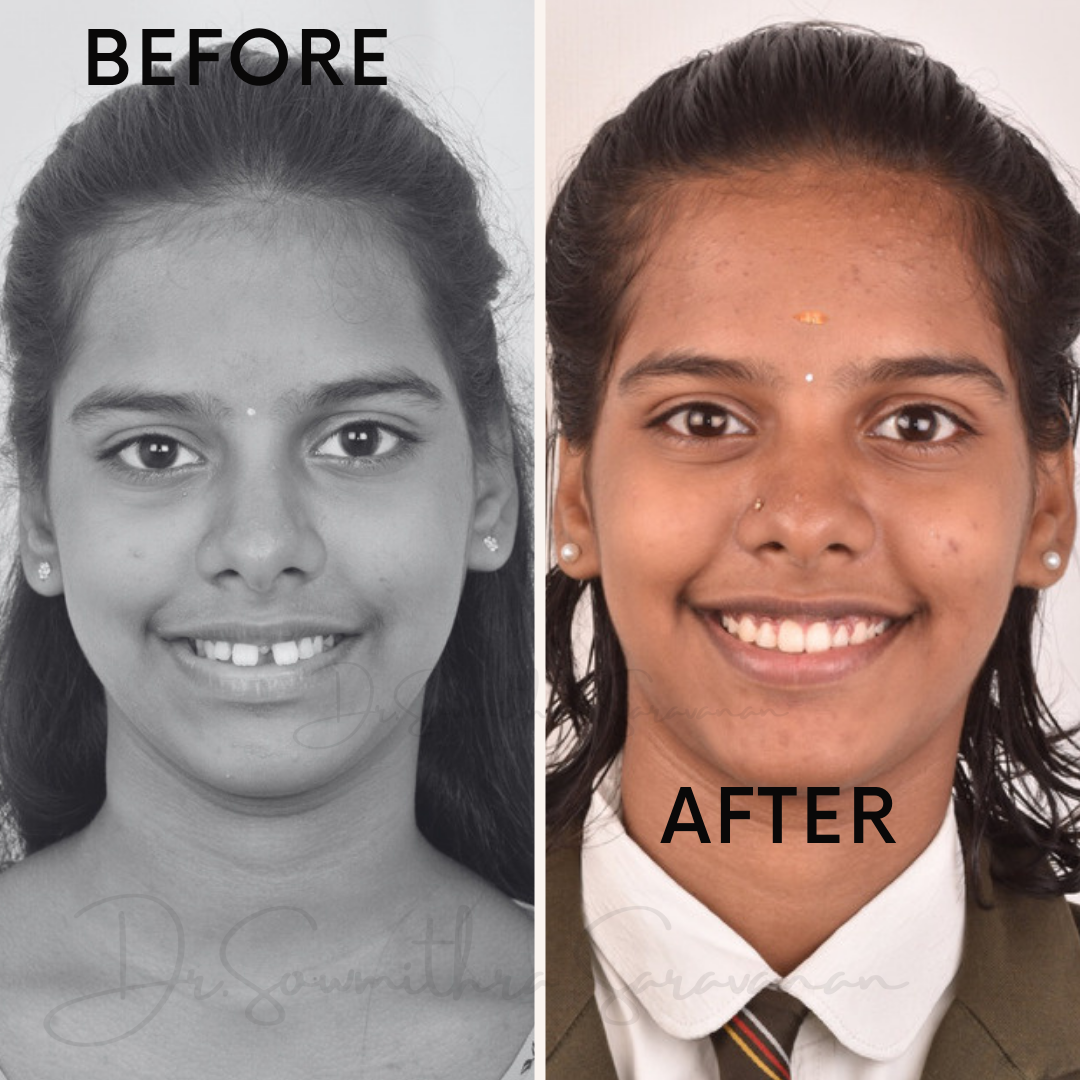

smile makeover

Smile Journey!

May be it is too simple to treat but the way this smile makeover made a difference in her life is immense! thats how wonderful smile curves are created!